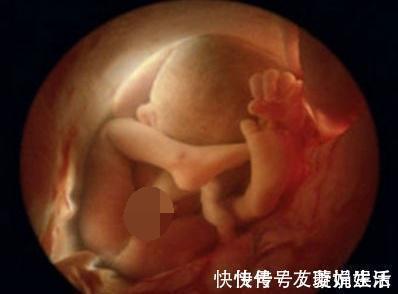

文章插图